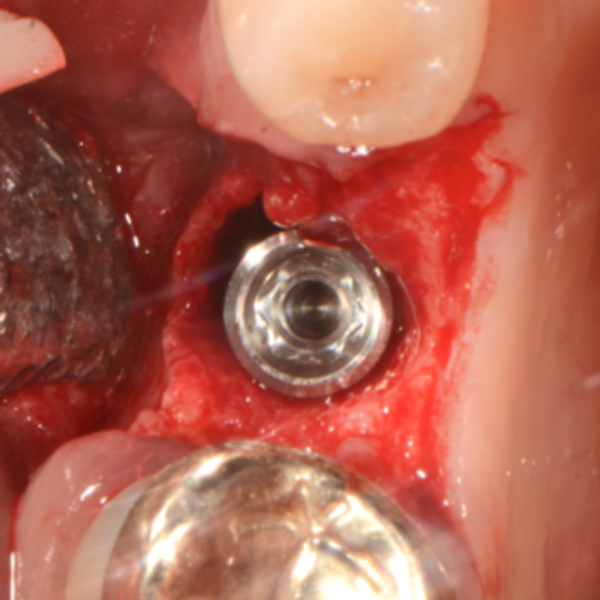

Immediate Dental Implant Placement

Tooth 14 slightly increased mobility, tenderness and bite pain. Suspected root fracture